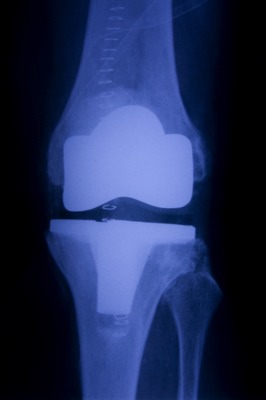

A total knee arthroplasty consists of resurfacing the bone ends of the knee joint when moderate to severe arthritis is present. A total knee replacement is usually recommended when there is a decrease in function, such as walking and stairs, secondary to increased knee pain. The joint surfaces are replaced with a metal cap and a plastic liner is inserted between the metal caps. After surgery your physical therapist will teach you how to move and use a walker correctly. As you progress with your recovery you will be instructed to complete a series of exercises to improve your range of motion and strength.

For more information regarding a Total Knee Arthroplasty visit: https://orthoinfo.aaos.org/en/treatment/total-knee-replacement/